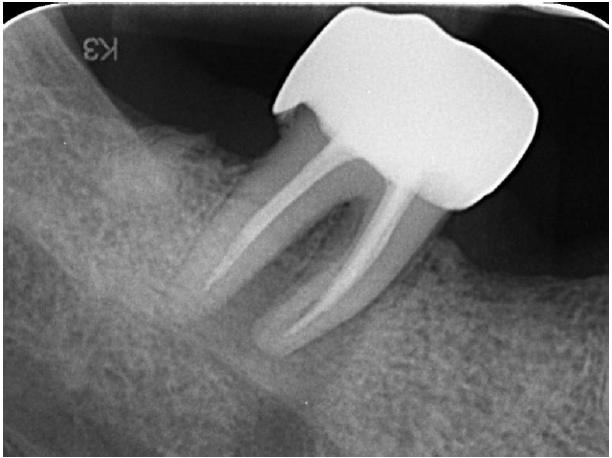

A 52-year-old male patient presented in 2021 with acute, severe pain localized to tooth 47 (mandibular right second molar). Clinical and radiographic examination revealed a large periapical lesion at tooth 47, despite the presence of a previous root canal treatment, and a compromised tooth 16 with extensive structural loss, subgingival decay, and perforation.

Large periapical lesion on tooth 47

Radiograph with initial treatment

OPG shows great healing on 47 at 4 years follow-up